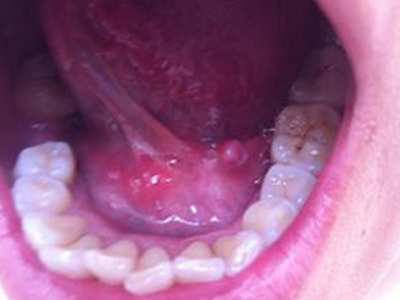

舌下腺囊肿舌头下面长了一个圆形肿块图

舌下腺囊肿位于舌底一侧,表现为圆形、光滑、柔软的肿块,直径约3cm大小,紧贴下牙,囊肿壁薄,呈浅紫蓝色,破裂并流出黏稠的液体。